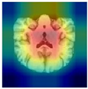

4.3. Grad-CAM Visualization Analysis

In the clinical application of deep learning models, model interpretability is a key factor for establishing trust among medical professionals and ensuring diagnostic reliability. To address this, Gradient-weighted Class Activation Mapping (Grad-CAM) technology is employed in this study, as shown in Table 6, to perform visualization analysis on the 3D DenseNet-121 model. This analysis reveals the model’s decision basis and its focus areas in the Alzheimer’s disease three-class classification task. Grad-CAM generates heatmaps that reflect the model’s attention distribution by calculating the gradients of the target class with respect to the last convolutional layer’s feature maps [27].

This technique can localize specific brain regions in MRI images where disease-related features are identified by the model, thereby providing an intuitive and quantitative basis for interpretation. The specific implementation process is as follows: first, 3D MRI images are inputted into the trained 3D DenseNet-121 model to obtain prediction probabilities for the AD, MCI, and CN classes; next, the feature maps from the final convolutional layer are extracted and class gradient weights are calculated; finally, a weighted combination of these weights and feature maps is performed, and the result is normalized and overlaid onto the original images to generate the visualization heatmaps.

Experimental results show that key brain regions highly associated with Alzheimer’s disease pathology are successfully identified by Grad-CAM as shown in Table 6. For AD classification, the model’s attention is primarily focused on regions known to be vulnerable to the disease, such as the hippocampus, entorhinal cortex, and medial temporal lobe. For MCI classification, the attention distribution is observed to cover structures around the hippocampus and parts of the frontal lobe, while a relatively uniform attention distribution is presented for CN classification, which reflects the overall integrity of normal brain tissue.

These visualization results not only validate the consistency between the features learned by the model and known Alzheimer’s disease neuropathological mechanisms, but also provide clinicians with an intuitive tool to understand the model’s predictive logic. Through Grad-CAM analysis, the clinical applicability and diagnostic reliability of the proposed multimodal fusion architecture are further confirmed, which lays an important foundation for the deployment of AI-assisted Alzheimer’s disease diagnosis in practical medical settings.

Table 6. Grad-CAM visualizations of brain MRI using the proposed model.

CNMCIAD

AxialElectronics 15 00367 i001Electronics 15 00367 i002Electronics 15 00367 i003

CoronalElectronics 15 00367 i004Electronics 15 00367 i005Electronics 15 00367 i006

SagittalElectronics 15 00367 i007Electronics 15 00367 i008Electronics 15 00367 i009

Note: Red colors indicate higher feature.